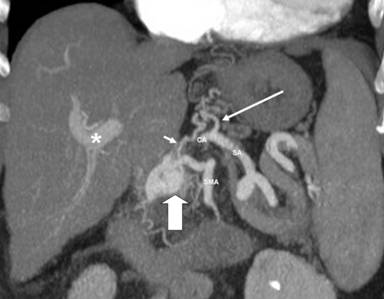

A 75-year-old female performed a quadriphasic abdominal CT examination for the characterization of a focal hepatic lesion, previously identified with a transabdominal ultrasound. Patient had a chronic HCV infection. The physical examination was substantially negative: particularly, the patient did not show any sign or symptom related to the pancreatic arteriovenous malformation or to gastrointestinal bleeding. The MDCT showed a hypervascular area of 3.5x2.5 cm in the pancreatic head, constituted of ectasic vessels (Figure 1); no calcifications were seen inside the mass. The lesion did not determine mass effect or dilation of the main pancreatic duct. During the arterial phase, there was also an early filling of the portal vein and the proximal portion of the superior mesenteric vein. Para-coronal maximum intensity projection and 3D electronic reconstructions made possible to identify the arterial afferents to the malformation (Figure 2), constituted by small aberrant branches from left gastric artery (Figure 3) and posterior inferior pancreaticoduodenal artery (Figure 4); it was also possible to identify the venous efferent drainage, constitute by the portal vein (Figure 5) and the superior mesenteric vein (Figure 6). Other MDCT findings were: presence of a cirrhotic liver with a solid 3.0x2.5 cm mass in the II segment, hyperdense in the arterial phase with washout during the portal phase, referable to hepatocellular carcinoma; an aberrant replacing right hepatic artery arising from the superior mesenteric artery; and a 1.5 cm solid hypodense lesion in the pancreatic body, with fat density and without contrast enhancement, referable to pancreatic lypomatosis.

Figure 3. Maximum intensity projection paracoronal arterial phase reconstruction image shows the pancreatic arteriovenous malformation (solid arrow) and its afferents (short arrow) arising from the left gastric artery (long arrow). Note the improper early appearance of intrahepatic portal vein (asterisk). CA: celiac artery; SA: splenic artery; SMA: superior mesenteric artery |